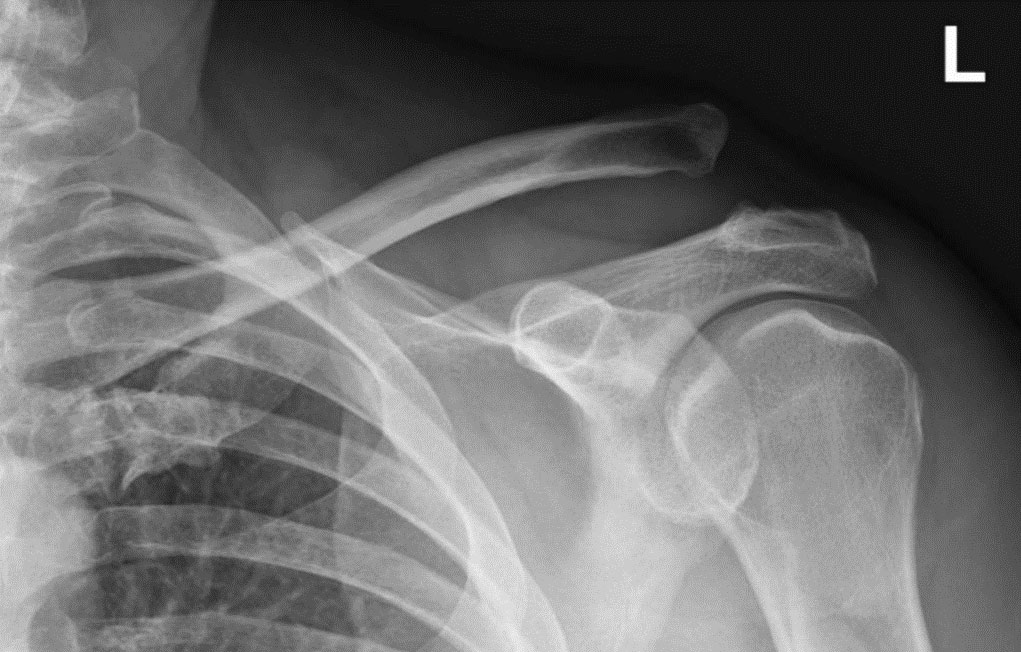

Tony is a 61 year old farmer, who lives in Rural NSW. His injury occurred when he fell off a horse and landed on his left shoulder. Tony presented to his local Emergency Department where he was complaining of left shoulder pain and an obvious lump. He was diagnosed of having an AC joint dislocation and had an X-ray was placed in a sling. He was given conflicting information as to what to do.

A week later, Tony attended my rooms and I noted that he had an obvious visible deformity to his left AC Joint. On examination, he had evidence of a Grade 3/5 Left AC Joint Dislocation, which was confirmed clinically and by Xray. He had collapse of his shoulder with loading his shoulder against resistance. This is typical of a significant disruption of your AC ligaments.

AC joint dislocation before surgery